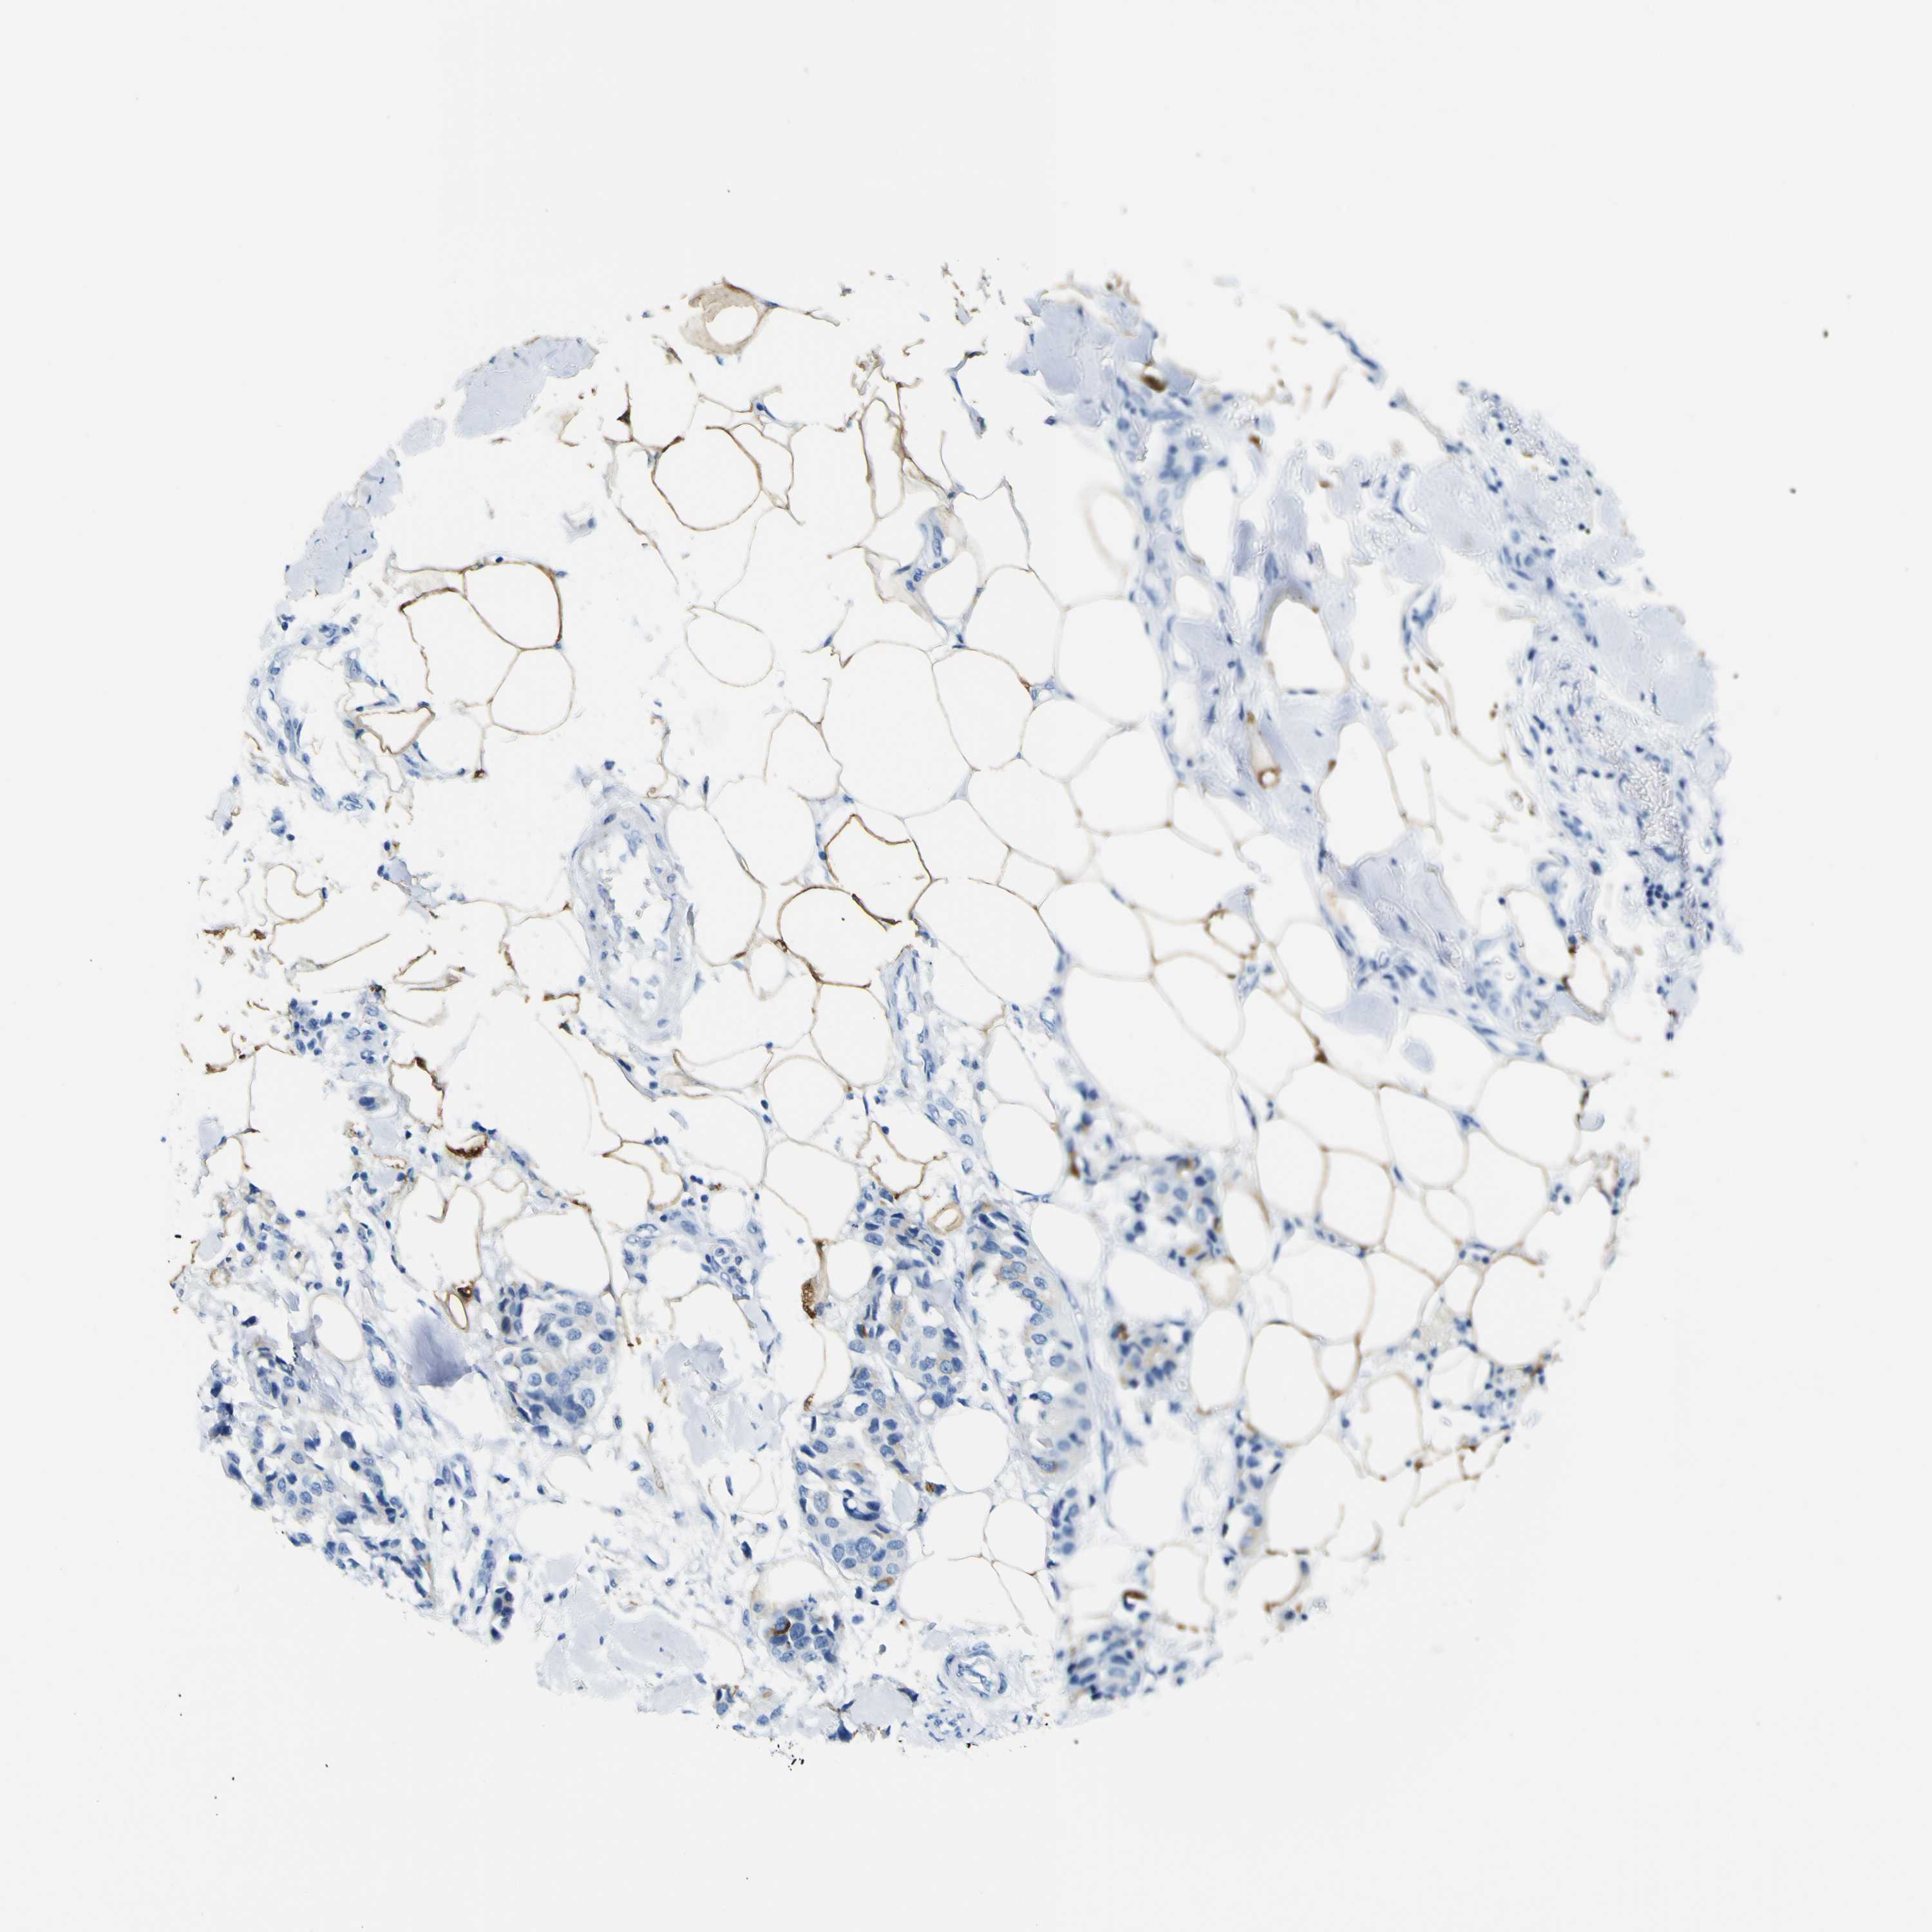

BRCA TCGA BRCA VALIDATION PROTEIN EXPRESSION

ANTIBODIES

AND

VALIDATION